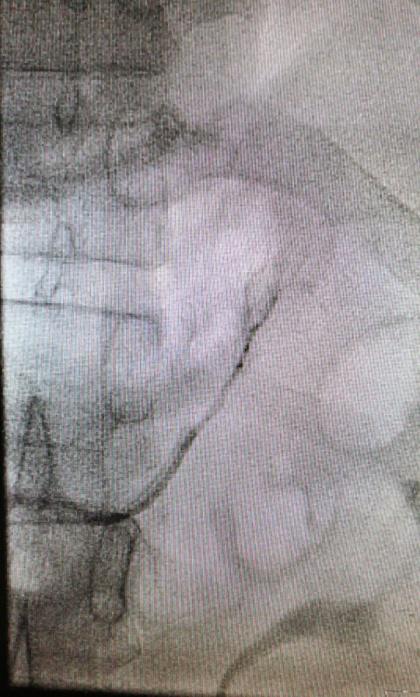

在征得患者及其家属的同意后,我院多科协作行双侧肾上腺静脉插管采血术。术中,仅仅在大腿根部局部皮肤麻醉,只需米粒大小一个针眼,通过股静脉将导管通过很多道弯曲,分别送达左侧和右侧肾上腺静脉。通过术中送检血皮质醇,证实双侧肾上腺静脉插管成功。然后,手术医生在双侧肾上腺静脉和下腔静脉同时取血。标本送检后,明确诊断为特发性醛固酮增多症,左侧肾上腺腺瘤无功能。患者无需手术,但需服用特殊的药物控制血压。在明确诊断后,心内科立即为患者调整了降压方案,针对特发性醛固酮增多症进行了针对性病因治疗。患者既往一直不能控制的血压迅速得到了良好控制。

右侧肾上腺静脉插管